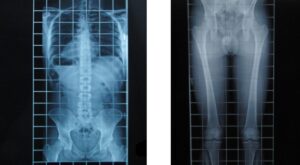

Telemetría, donde se puede apreciar la diferencia ósea de las extremidades inferiores del paciente